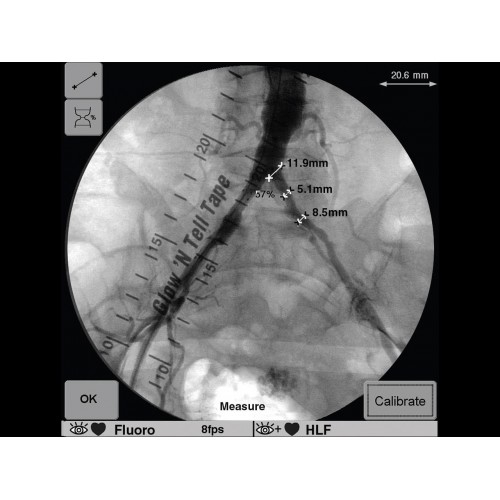

Инновационная мобильная С-дуговая система для интраоперационной визуализации с высоким разрешением. Обеспечивает хирургов качественным изображением в реальном времени при минимальной лучевой нагрузке. Усовершенствованная эргономика позволяет легко позиционировать аппарат в условиях операционной. Поддерживает интеграцию с современными хирургическими навигационными системами.

Передовая рентгенохирургическая система GE OEC 9900 Elite представляет собой инновационное решение для проведения широкого спектра малоинвазивных вмешательств. Это оборудование премиум-класса сочетает высочайшее качество визуализации с интуитивно понятным управлением, устанавливая новые стандарты в области интраоперационной рентгеноскопии.

GE OEC 9900 Elite оснащен революционной системой визуализации, обеспечивающей кристально четкое изображение анатомических структур. Интеллектуальная система автоматически адаптирует параметры исследования под конкретную хирургическую задачу, обеспечивая оптимальный баланс между качеством изображения и лучевой нагрузкой. Особое внимание уделено удобству работы операционной бригады.

В ведущих медицинских центрах GE OEC 9900 Elite успешно применяется для проведения сложных кардиологических, нейрохирургических и ортопедических вмешательств. Система доказала свою эффективность при выполнении стентирования коронарных артерий, эмболизации сосудов головного мозга и вертебропластики. Многие учреждения отмечают повышение качества операций после внедрения этого оборудования.